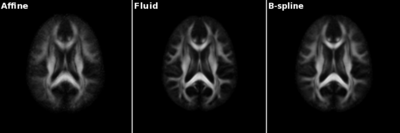

|valign="top"|[[Image:Gcasey-atlas-slices.png |thumb|400px|Slices from atlases built with only affine registration, fluid registration, and b-spline registration]]

Slices from atlases built with only affine registration, fluid registration, and b-spline registration